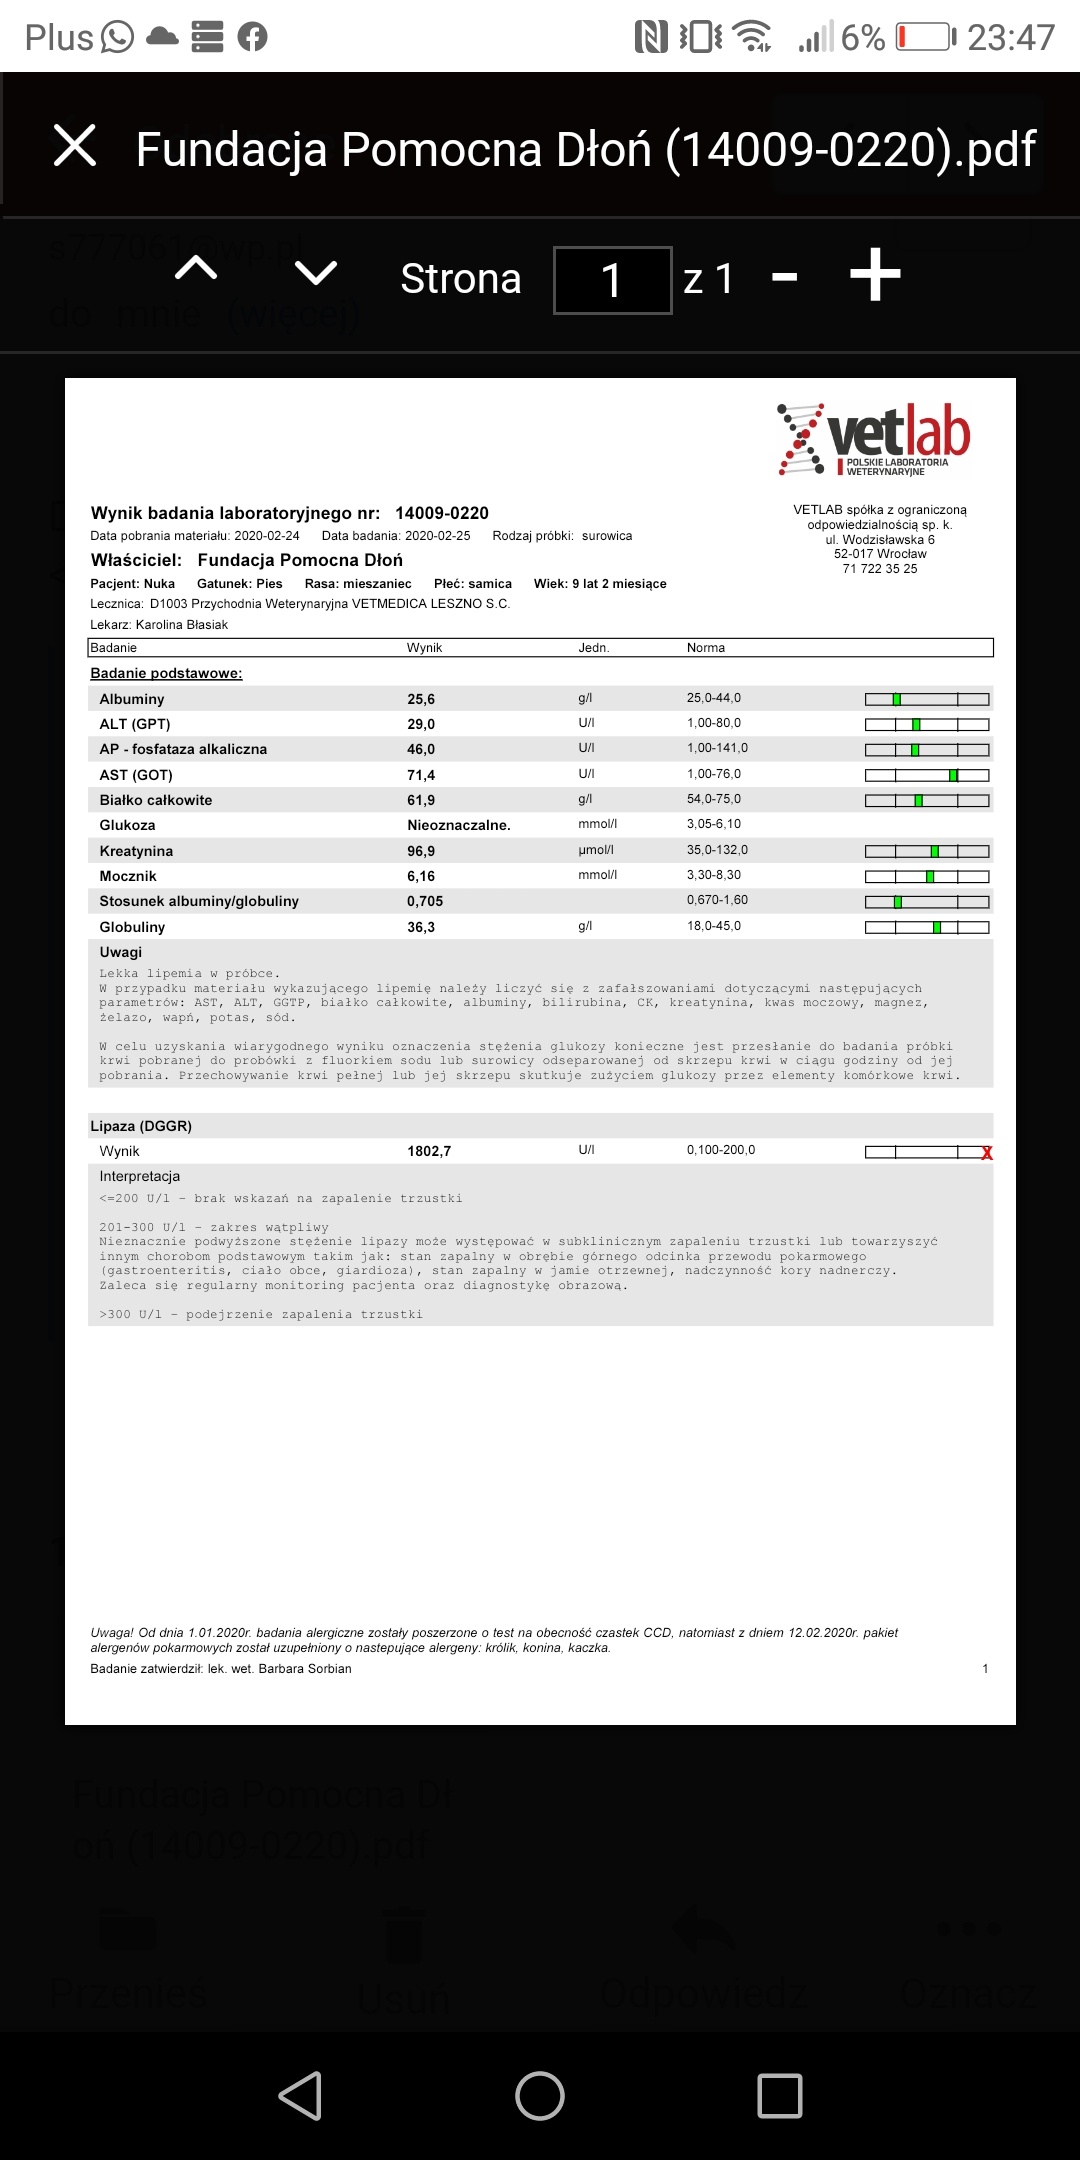

Kochani ta zbiórka jest założona na utrzymanie i leczenie suni Nuki zabranej z fatalnego przytuliska do hotelu by nie trafiła do schroniska. W hotelu przebywa już prawie 4 lata. Jest już starsza sunia... Takie psiaki maja małe szanse na adopcję. Dodatków problemem Nuki było nieakceptowanie małych dzieci. Nie mogliśmy jednak pozwolić by zginęła w schronisku. Czas nie oszczędza jednak Nuki i poglebily się problemy zwyrodnieniowe oraz doszło zapalenie trzustki. Nuka by żyć bez bólu musi dostawać lek o nazwie cimaglex 80 mg. Miesięczny koszt leczenia to 200 zł. Do tego musi jeść karmę niskotłuszczowa dla trzustkowcow. Koszt karmy takiej weterynaryjnej to ok. 250 zł.